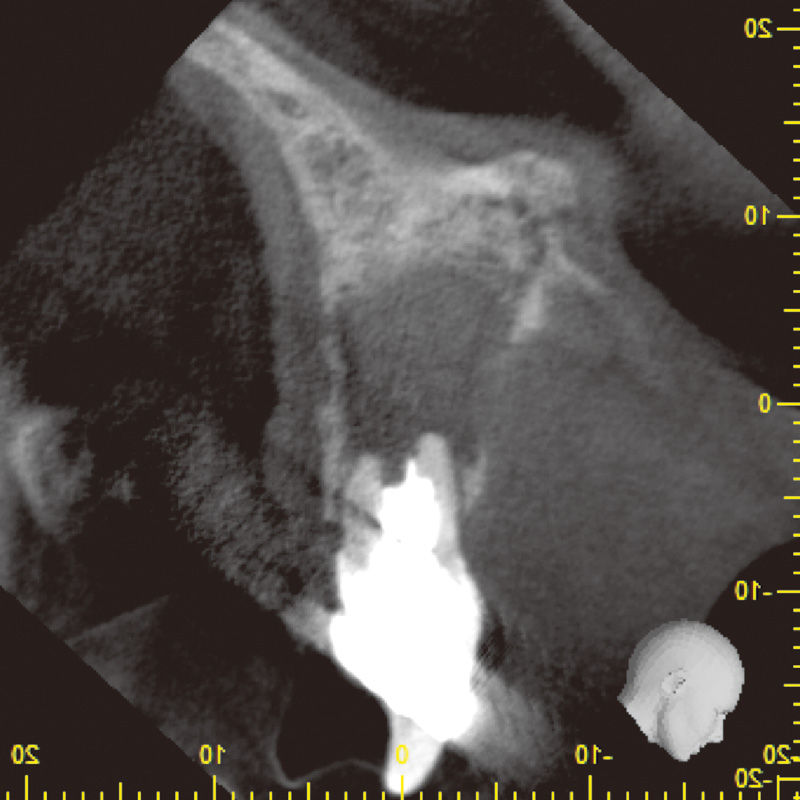

患者は35歳男性で主訴は咬合痛であった。自発痛(-)咬合痛(+)・打診痛(+)・根尖部腫脹(中等度)根尖圧痛(軽度)であり、デンタル及びCBCTでは根尖部透過像・著明な外部吸収及び根尖孔破壊・根管充填材・太いポストコア及び根管壁の菲薄化を認めた(症例1-1, 1-2)。

症例1-2 初診時CBCT画像( Veraviewepocs 3Dfにて撮影)![[写真] 多量の排膿](/academic/dentalmagazine/wp-content/uploads/sites/2/2025/11/195-6_photo03.jpg)